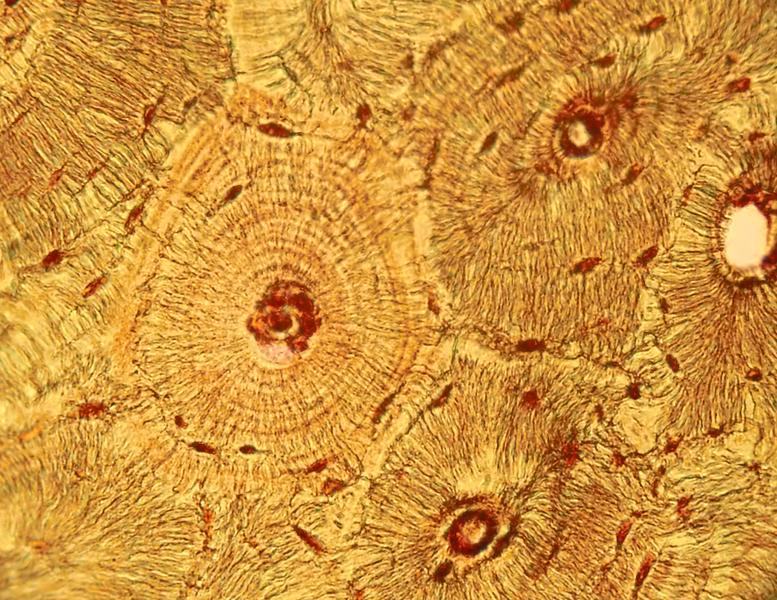

Структура грубоволокнистой костной ткани: наглядные примеры